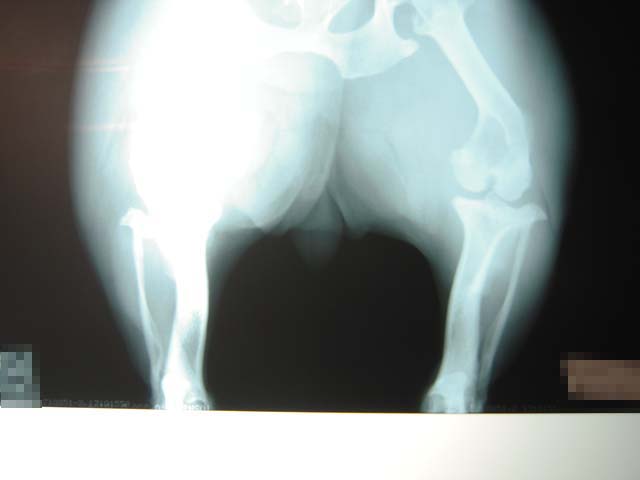

両後ろ足とも手術していますが、冬になるとやっぱり膝の痛みが出やすくなります。走った後に足を少し上げたりするので再度レントゲンでチェック。関 節炎が少しでてきているということです。この写真ではあまりよく見えませんが、関節の間に炎症が少し白っぽく映っていました。足に極度の負担がかかる運動 は注意しないといけません。